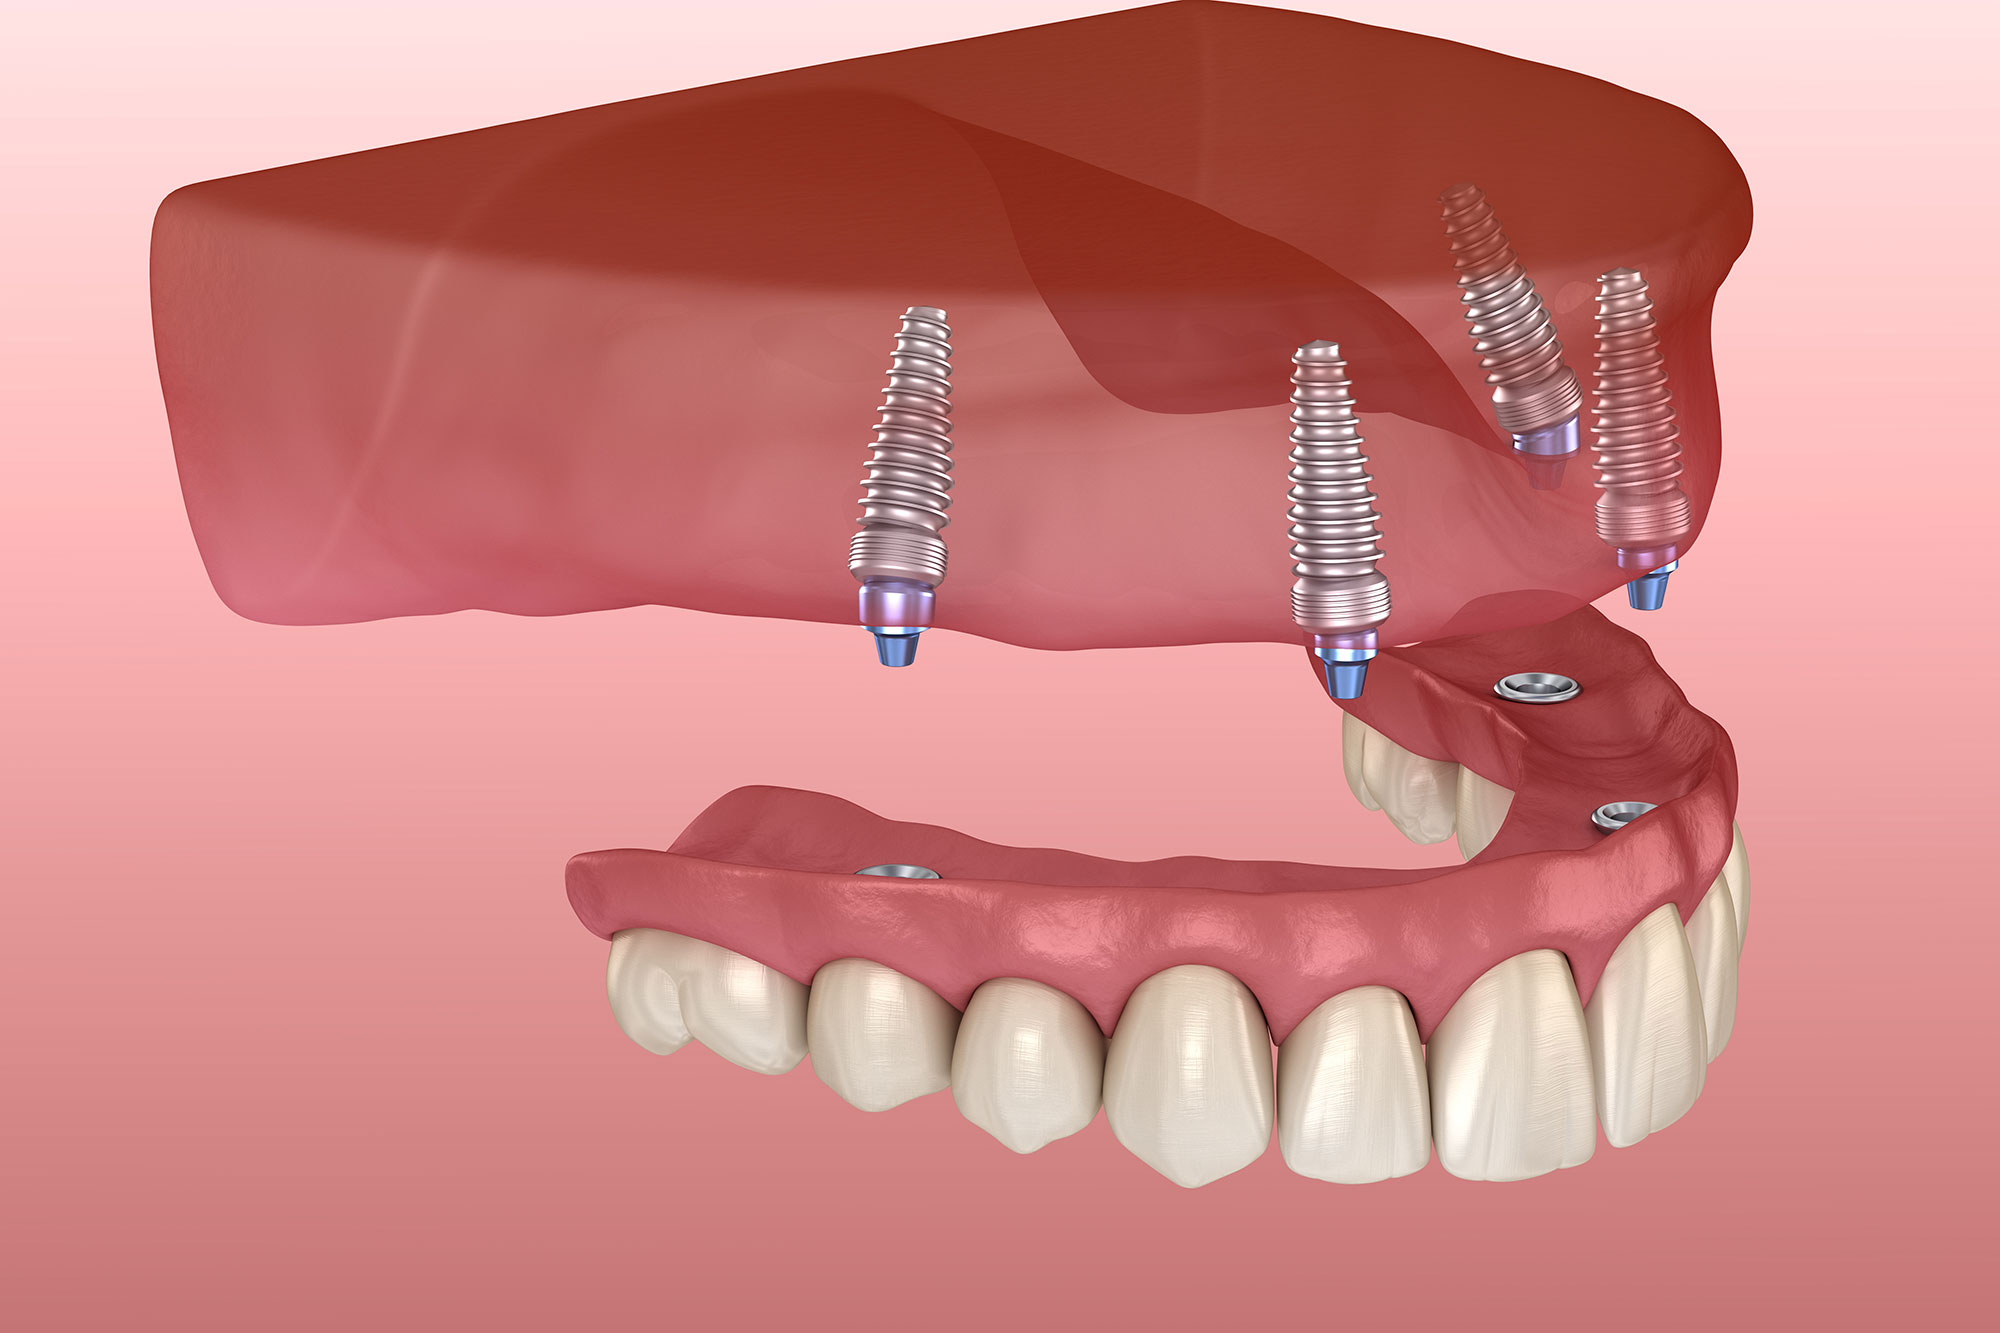

Ceramic implant crown

Ceramic implant crowns are dental crowns specifically designed to attach to dental implants, serving as replacements for missing teeth with restorations that closely resemble the appearance and functi...

Screw Retain Implant Crown

A screw-retained implant crown is a type of dental crown fixed to a dental implant with a screw instead of dental cement. This approach is frequently utilized in implant dentistry due to its benefits...

Zirconia Implant Crown(5 Year Warranty)

A zirconia implant crown is a specific type of dental crown designed to be placed on a dental implant, made entirely from zirconia ceramic. Zirconia is recognized for its strength, durability, and aes...

Implant Crown

An implant crown is a dental prosthetic designed to replace a lost or extracted tooth, utilizing a dental implant as its supporting structure. The implant crown is fitted on top of the dental implant,...